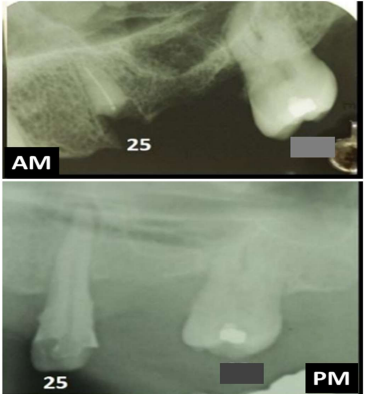

As radiografias odontológicas possuem grande importância para a identificação humana, pois podem exibir particularidades anatômicas, terapêuticas e patológicas específicas de um indivíduo, cujo corpo não pode ser identificado pelas impressões digitais, como nos casos de corpos carbonizados, putrefeitos e em decomposição avançada. Para subsidiar uma identificação utilizando-se radiografias odontológicas torna-se importante reproduzir no exame pós-morte (PM) as mesmas estruturas evidenciadas no exame produzido antes da morte (AM). Sobre os aspectos técnicos e periciais inerentes a uma identificação radiológica odontológica, analise as afirmativas a seguir, tendo como base uma adaptação realizada no confronto radiográfico AM e PM do trabalho publicado por Pereira e colaboradores (2021), sabendo-se que o lapso temporal entre as radiografias AM e PM é de cerca de 4 anos.

I. Neste confronto radiográfico AM x PM, há 5 similaridades considerando os dentes presentes e ausentes. II. Uma das similaridades anatômicas é a ausência do dente 28 (perda antiga) e uma similaridade terapêutica é a presença de material restaurador no dente 27. III. Por haver pelo menos 6 similaridades e uma discrepância explicável no dente 25, a identificação pode ser positiva. IV. Mesmo havendo pelo menos 6 similaridades, a presença de uma discrepância inexplicável no dente 25 remete a uma exclusão.

Fonte: imagem adaptada do artigo científico de autoria de Pereira e colaboradores (2021), publicado na Revista Brasileira de Odontologia Legal, v. 3, n. 8, p.95-102.